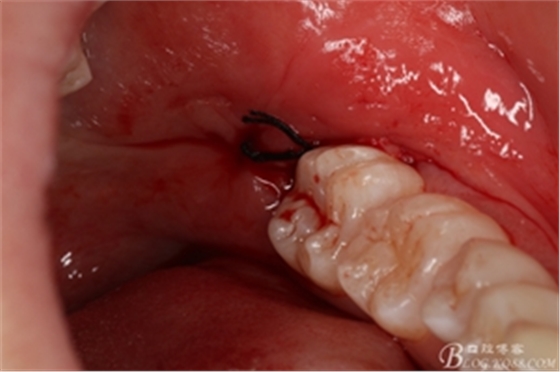

圖16. 38的牙根完整取出,對(duì)下頜神經(jīng)管未施加壓力

圖17. 縫合